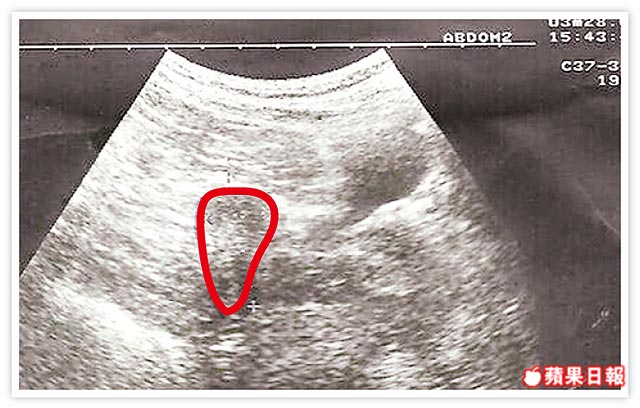

結核菌吃子宮奇蹟懷孕

婦作11次試管嬰兒才成功 醫界驚異

2005年04月27日